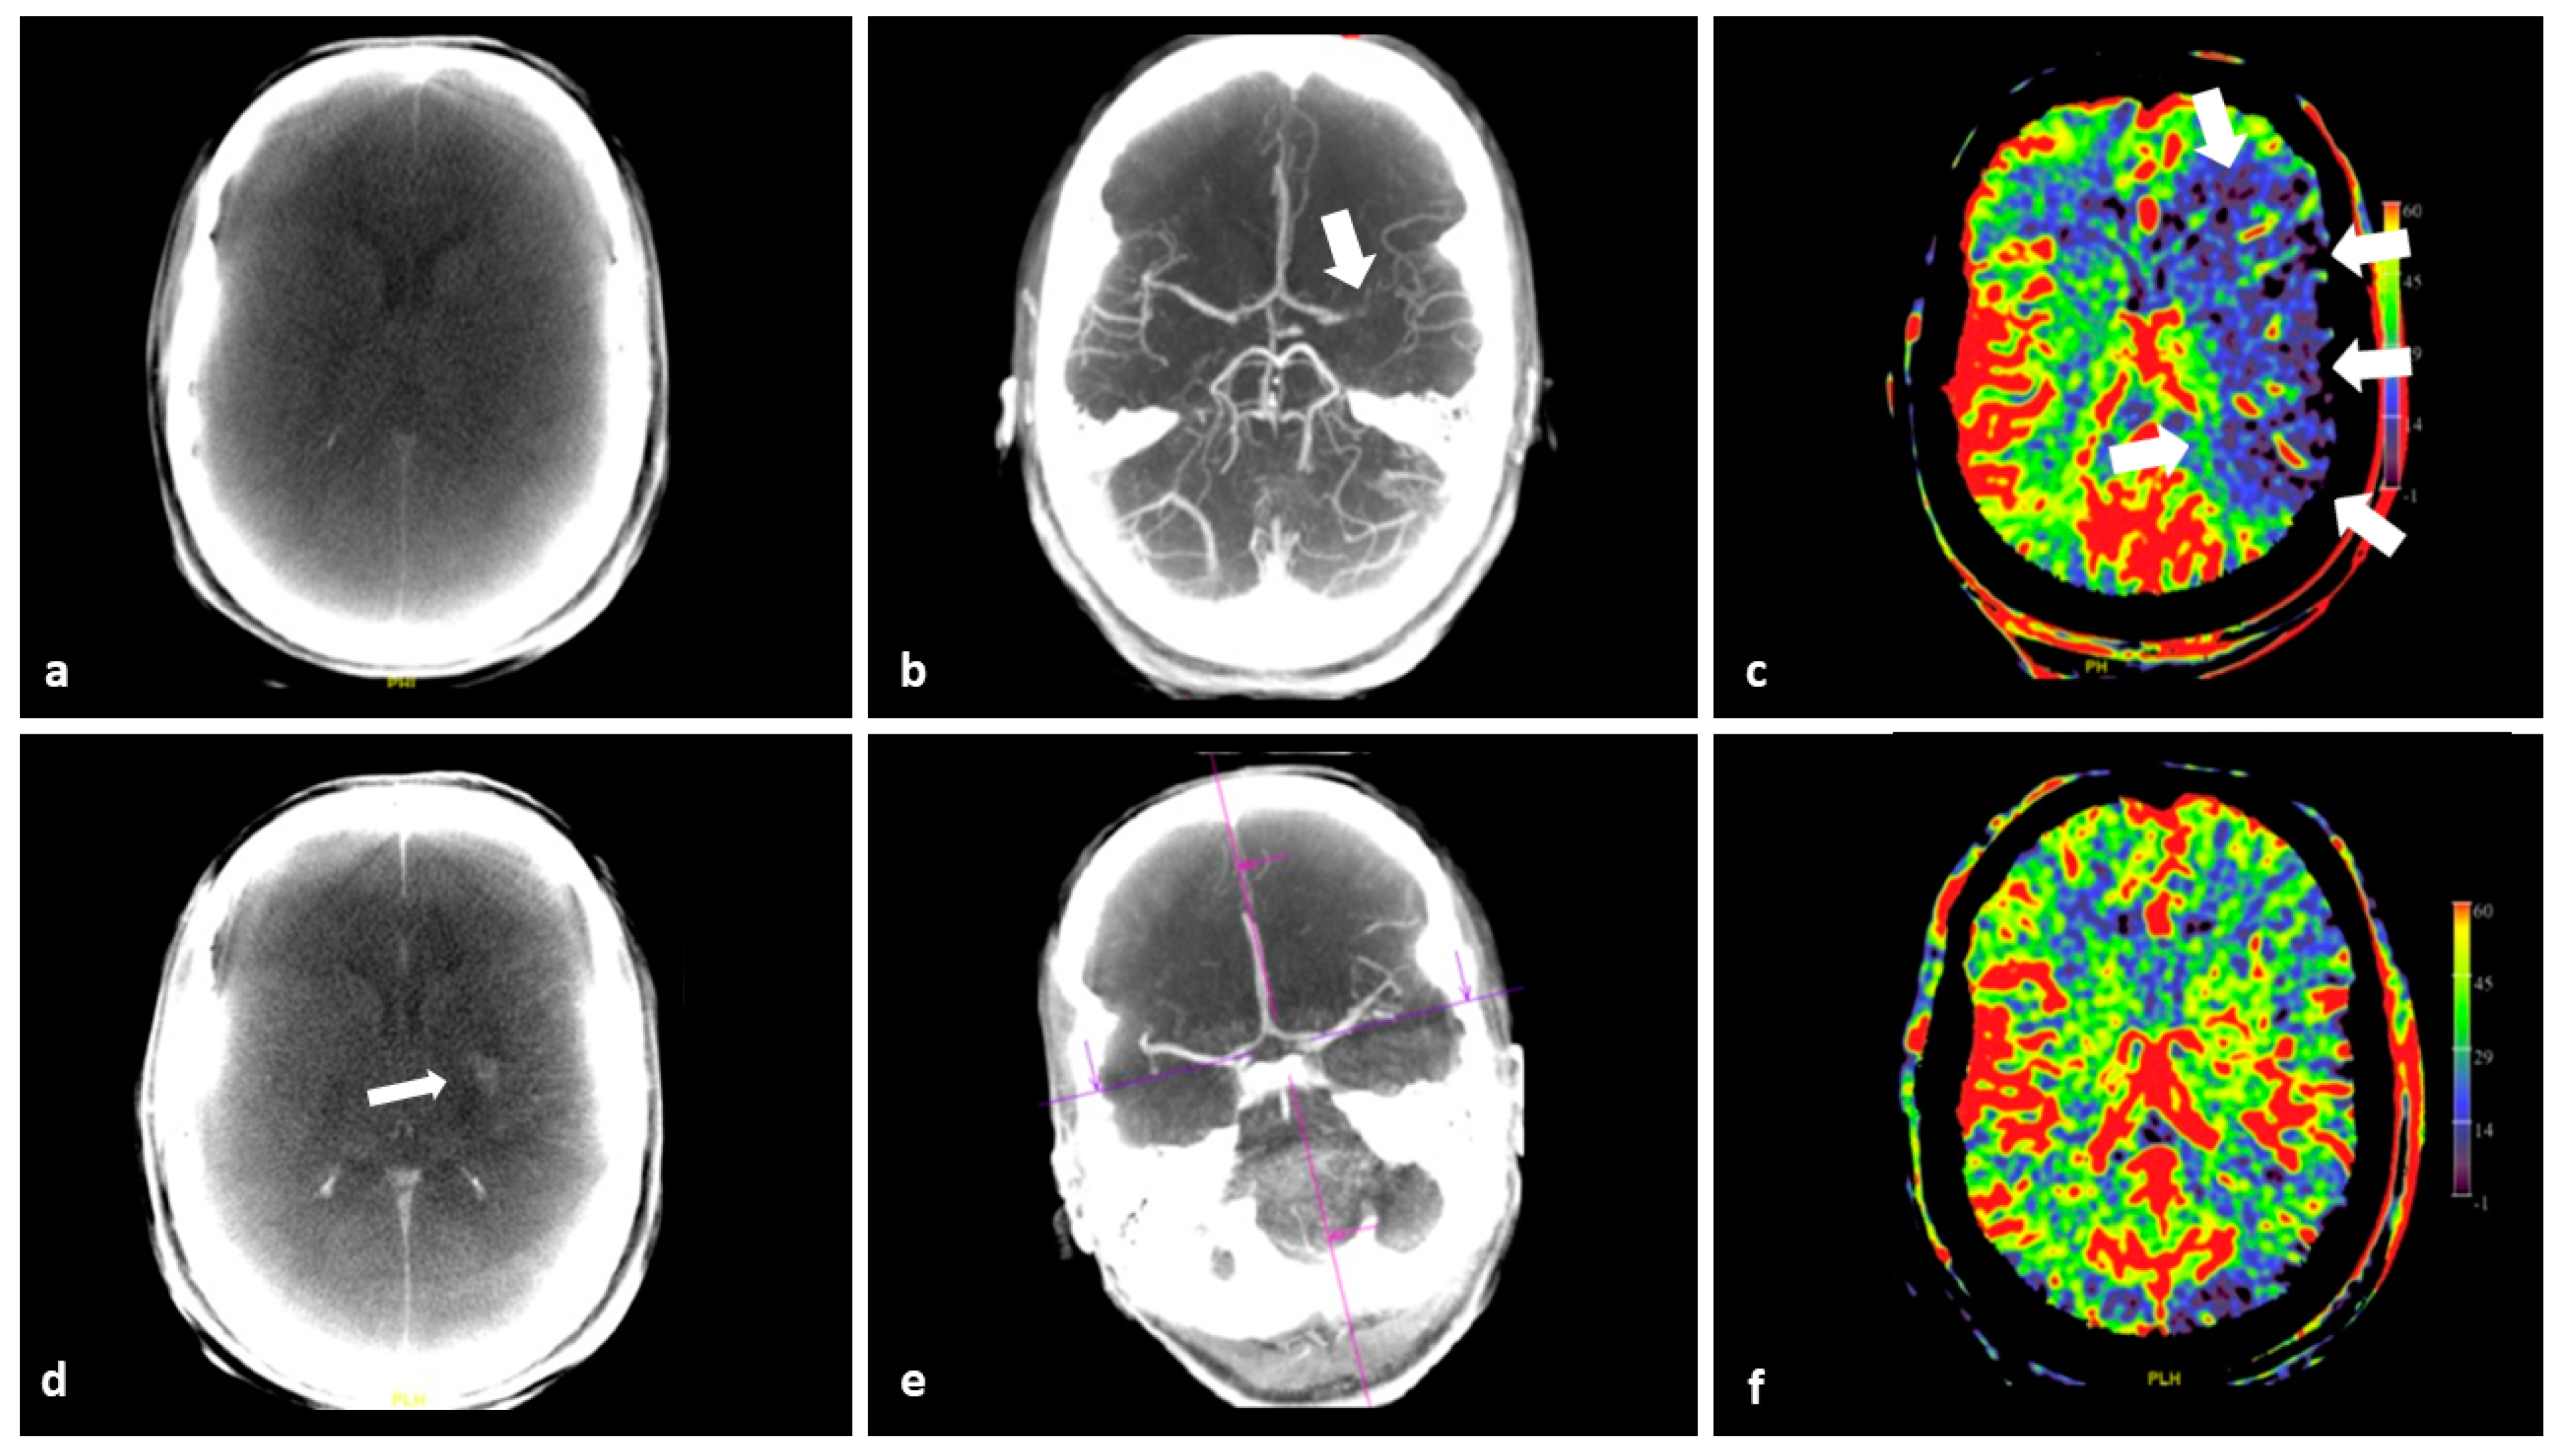

Timely and adequate imaging is pivotal to ensure a good clinical outcome in the treatment of AIS patients [3,22,23]. The first step is to rule out hemorrhage and significant early ischemic brain parenchymal changes, in order to start appropriate treatment as quickly as possible. It is recommended to perform vessel imaging to select patients with LVO for endovascular thrombectomy (EVT) [24]. In current clinical practice, these imaging steps are performed by conventional MD CT or MRI as soon as possible. Nowadays, it is feasible to perform all the necessary imaging in the angiography suite thanks to the use of FD CT imaging, thus enabling a “one-stop-shop” approach in management of AIS patients [12,25]. Advanced imaging in the work-up of AIS patients within <6-h time interval from symptom onset to imaging should not delay recanalization treatment [24]. Therefore, it is not strictly recommended for selecting patients for EVT in <6 h. However, in late-presenting or wake up stroke patients, additional perfusion and/or MRI diffusion weighted imaging (DWI) is endorsed to appreciate the ratio of potentially salvageable brain tissue to already infarcted brain tissue [24]. If there is a significant time delay between initial stroke work up imaging and EVT, for instance because the patient requires transportation from the primary stroke center to a comprehensive stroke center, or in cases of significant alteration of the clinical status of the patient, additional imaging, including perfusion imaging, can be very useful [25]. FD CT PBV imaging not only provides perfusion PBV images, but also mask run images and fill run images, which can be used to detect brain parenchymal and vascular abnormalities, respectively, as demonstrated in Figure 2.

Figure 2.

FD CT imaging in a 44-year-old female with AIS due to LVO, referred for EVT. (a) Pre intervention axial MIP reformation of the mask run demonstrates no hemorrhage. (b) Pre intervention axial MIP reformation shows occlusion at the level of M1-segment of the left MCA (arrow). (c) PBV MIP reformation features a perfusion deficit in the left MCA supply area (arrows). (d) Post EVT axial mask run MIP reformation demonstrates small area of contrast pooling in the left lentiform nucleus and the revascularized MCA territory (arrow). (e) Post EVT axial fill run MIP reformation confirms recanalization. (f) Post EVT axial PBV MIP reformation shows restoration of CBF with (almost) symmetrical PBV map.